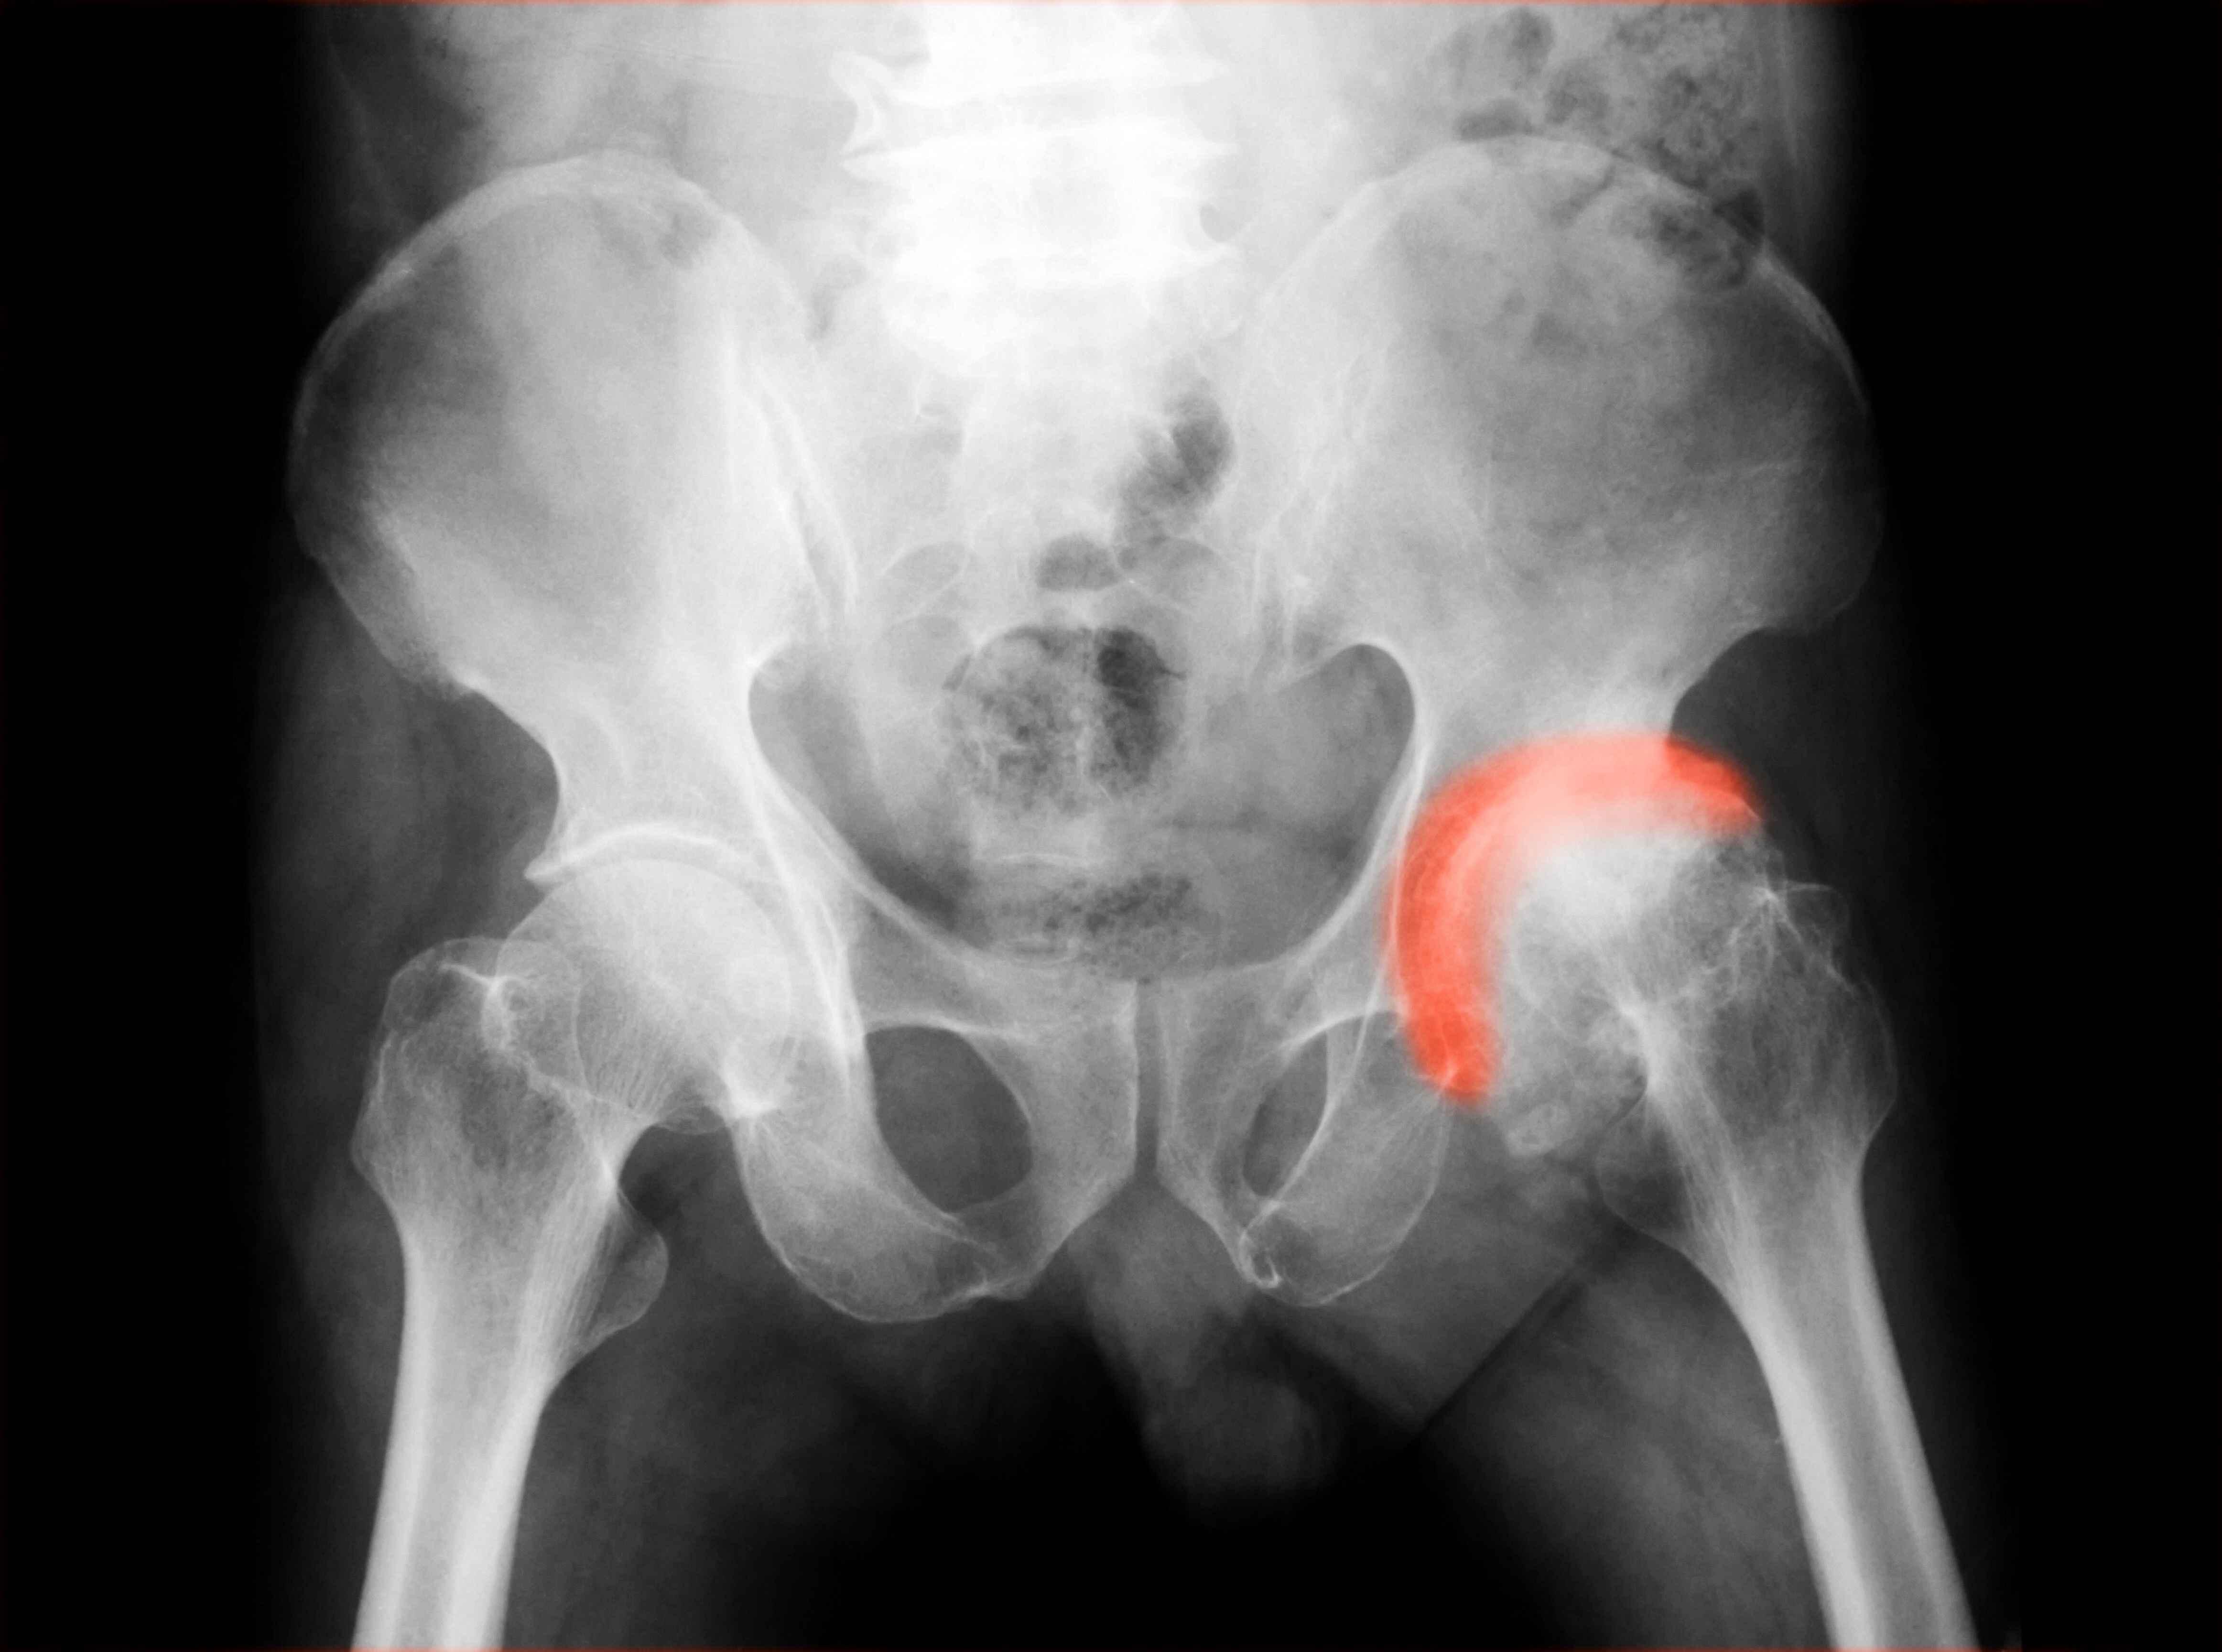

從定義上看,股骨頭壞死指的是骨小梁結構遭受損傷之後引起的股骨頭塌陷或者變形情況。

具體來看,如果髖關節不小心出現了骨折或者脫位的情況,那麼很容易就會導致股骨頭的血管受到損傷。如果這時候患者沒有及時對其進行處理,那麼很可能就會導致股骨頭缺血,從而引發股骨頭壞死的問題。